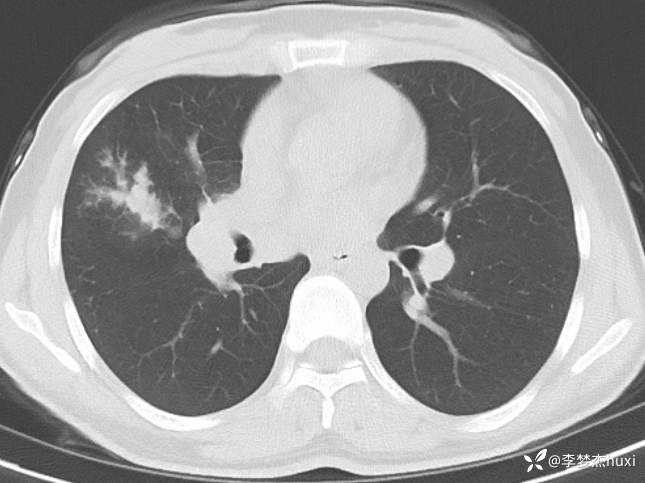

女性35岁,主因咳嗽、咳痰1月,胸部CT报肺炎,猜对乃神医!

女, 35 岁,主因咳嗽、咳痰1月于2025-11-05 08:46入院。

1.现病史:患者中年 女,患者于入院前1月“感冒”后出现咳嗽、咳痰,为黄白痰,不易咳出,无痰中带血,咽部刺痒不适,咳嗽明显,无胸痛,无胸闷、憋气,无恶心,未呕吐,无腹痛、腹泻,无尿频、尿急、尿痛,于院外口服药物(具体不详)治疗,病情未见好转,2025-11-4于我院门诊查胸部CT提示右肺炎症。为进一步诊治来我院;门诊以“肺炎”收入院 。

3.查体:T36.5℃,P90次/分,R18次/分,BP105/65mmHg。神清,呼吸平稳,浅表淋巴结不大,双肺叩清音,双肺呼吸音粗,右肺可闻及湿性啰音,左肺未闻及干湿性啰音,心率90次/分,心律齐,无杂音。腹部平坦软,全腹无压痛,无反跳痛及肌紧张,肝脾肋下未触及,双下肢无水肿。

肺炎。